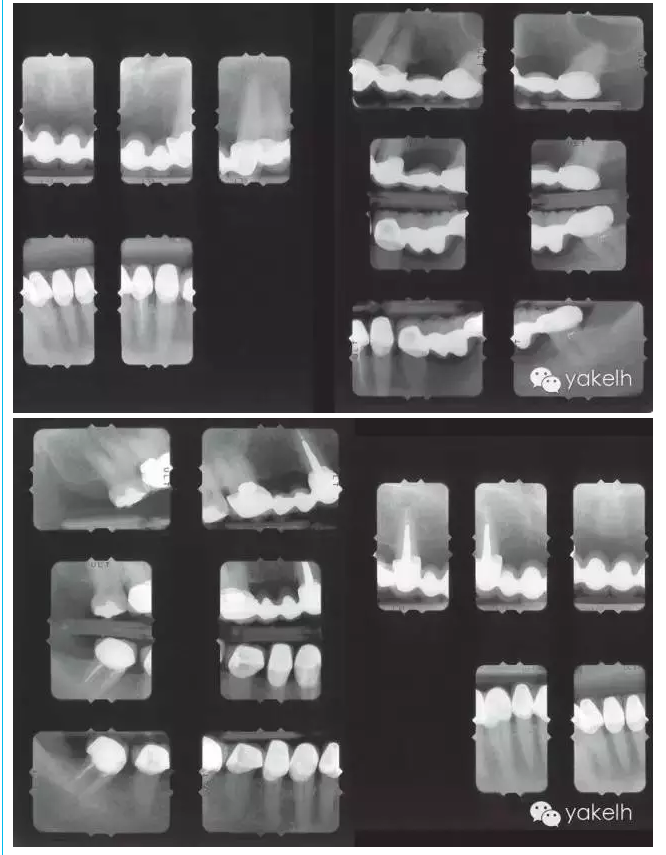

上頜天然牙牙支持式固定橋更換為種植體支持式固定橋,其他用單冠及牙支持式固定橋修復(fù)(病例)

¤¤因關(guān)鍵基牙遠(yuǎn)期預(yù)后較差,臨床上經(jīng)常需要將牙支持式固定橋換成種植體支持式固定橋。治療的困難在于整個(gè)治療過(guò)程中因?yàn)榛颊卟荒芙邮芑顒?dòng)的暫時(shí)修復(fù)體,需要制作固定的暫時(shí)修復(fù)體。該患者在其他國(guó)家進(jìn)行了整個(gè)牙合重建。但對(duì)結(jié)果不滿意,也不喜歡美學(xué)效果,上唇過(guò)于凹陷,咬合也不舒適。此外,修復(fù)體結(jié)構(gòu)和邊緣適合也不足,需要全部更換。部分牙齒缺失,并且關(guān)鍵基牙—右上尖牙,遠(yuǎn)期預(yù)后差。因此,治療計(jì)劃包括植骨在內(nèi)的口腔種植手術(shù)。

檢查和診斷要點(diǎn)

牙列

原修復(fù)體形態(tài)和功能不良

右上尖牙是關(guān)鍵基牙,但遠(yuǎn)期預(yù)后差